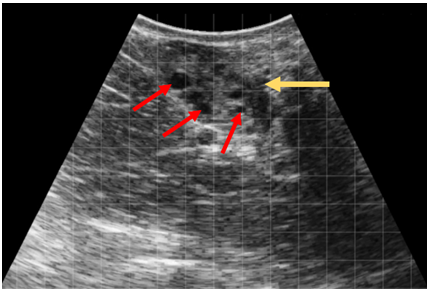

What are the red arrows pointing to?

Follicle from ultrasound (cow)